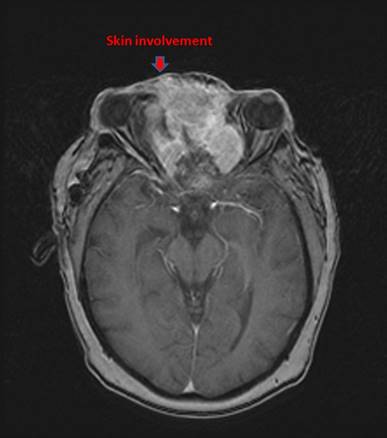

All patients were staged with head-neck computed tomography (CT) initially and magnetic resonance imaging (MRI) additionally in recent years. The diagnosis suspected on CT and/or MRI was pathologically proven with biopsy. Both Kadish/Morita staging system and American Joint Committee on Cancer (AJCC) stage (2002) were recorded. Of note, nine patients presented with cervical lymph node (LN) metastases ipsilaterally, with other three patients bilaterally involved. Four patients, who had local skin involvement was classified as stage D according to the Kadish/Morita stage system (Fig. 1). MRI and/or CT scans were routinely applied to assess tumor response to chemotherapeutic agents.

Figure 1

MRI of a patient with an unresectable esthesioneuroblastoma who presented with proptosis, lateral deviation of the left eye.

Survival in association with skin involvement at initial diagnosis

However, Patients with skin-involved ENB demonstrated significantly poorer 5-year overall survival (0% vs.45.5%, P=0.038) and 5-year progress-free survival (0% vs. 31.3%, P=0.001) than those without skin involvement (Fig.3G, I).

Among four patients with skin involvement, the median survival time was 22 months. All those patients presented with local relapses (100%), of whom two cases demonstrated a regional relapse. Although salvage chemotherapy or surgery was administered, all of them died from tumor progression.